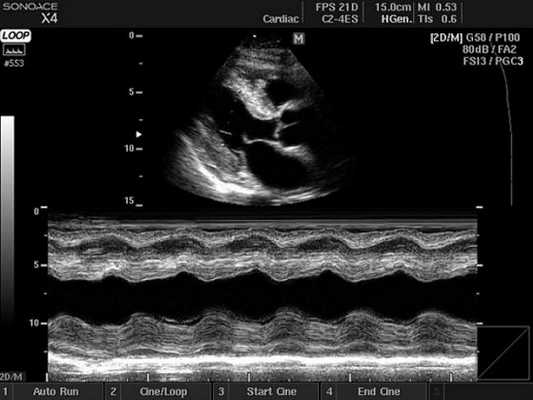

Основные режимы визуализации, применяемые при УЗИ сердца

Ультразвуковое исследование сердца в основном используется для получения двухмерного изображения этого органа и близлежащих магистральных сосудов. А также с помощью этой методики можно оценить скорость и направление кровотока, что требует применение эффекта Допплера. В зависимости от того, как обрабатывается и отображается на мониторе эхо-сигнал, различают следующие режимы ЭхоКГ:

- Двухмерный (2D режим). На монитор выводится изображение сердца в разрезе (в двух измерениях). Данный способ является основным при визуализации этого органа, позволяет детально рассмотреть анатомические отклонения и аномальные движения миокарда, клапанов.

- М-режим (M-mode). Это «усеченный» вариант предыдущего, при котором используется для анализа только одномерное изображение. Основное внимание уделяется одной из линий 2D трассировки, что позволяет более детально исследовать движения створок клапанов и сердечной мышцы.